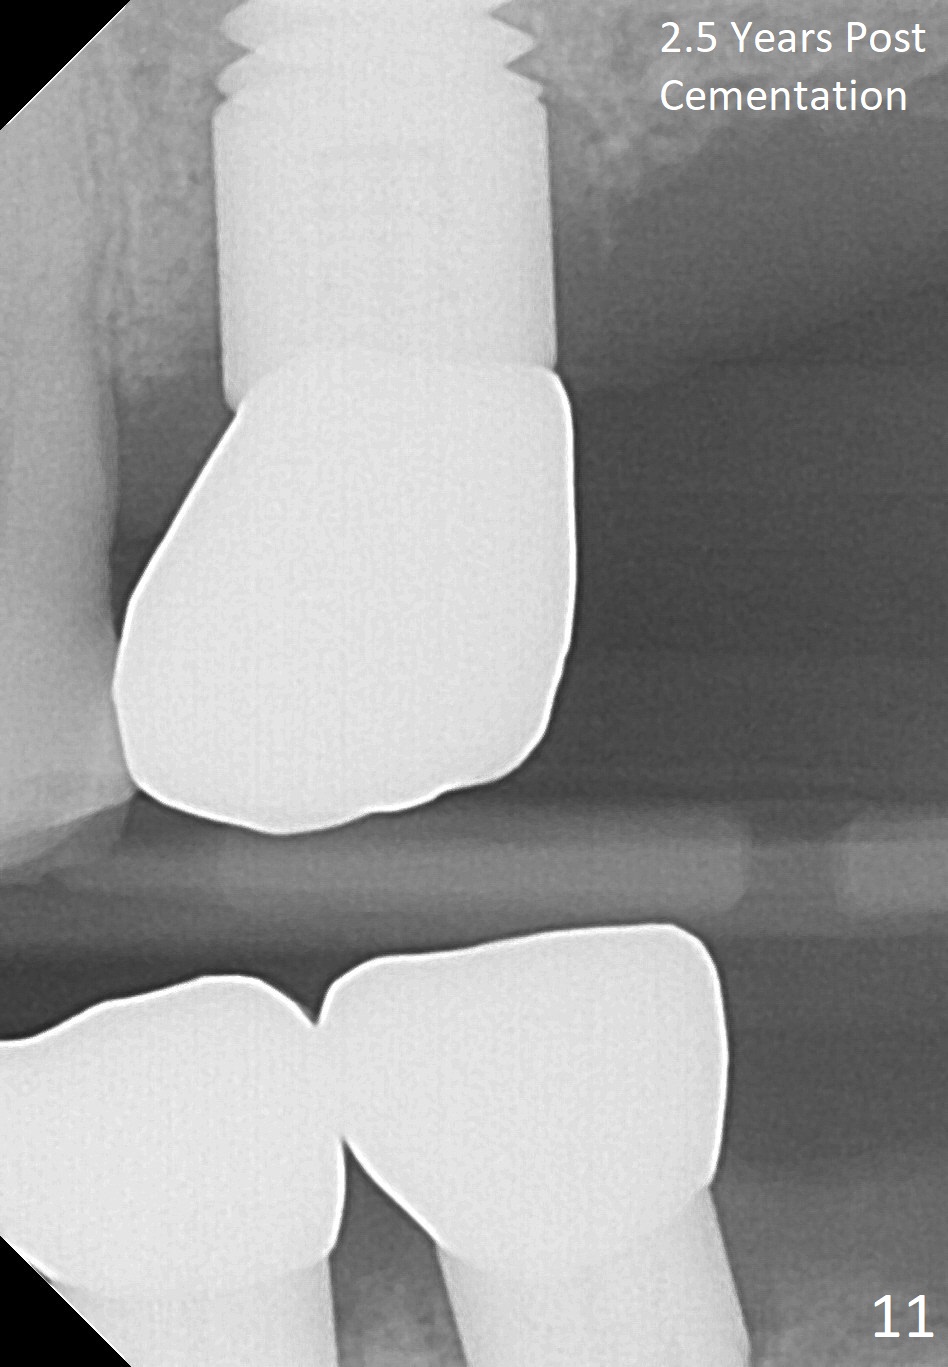

Fig.5 is an illustration showing the socket after extraction. The osteotomy is intentionally placed distally (Fig.6 arrow: pilot drill). In case the patient agrees to have ortho treatment, there will be space to correct the upper midline (7). If not, a molar crown will be fabricated. By the time a 4.5x20 mm tap is inserted (Fig.7 T), the mesial gap is visible (*). When a 6x20 mm implant is placed (Fig.8 I), bone graft is placed buccally (Fig.2, as planned) and mesially (Fig.8 red circles, as compared to Fig.1). The implant has to be as large and long as 6x20 mm to get primary stability (insertion torque 50/60 Ncm). The apex of the implant is close to the sinus floor (Fig.8 ^) or in fact the nasal floor (Fig.9 N). There appears bone growth in the mesial gap 3 months postop (Fig.10 *). There is no bone loss 2.5 years post cementation (Fig.11).

CT taken 4 years 9 months post cementation shows that the coronal portion of the buccal plate regenerates (Fig.12 between arrowheads, as compared to Fig.2,9). The density is ~1,000 Hounsfield Units, as compared to ~2,000 HU of the apical portion (Fig.13).